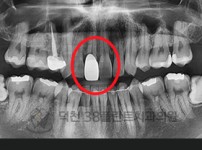

치료전후